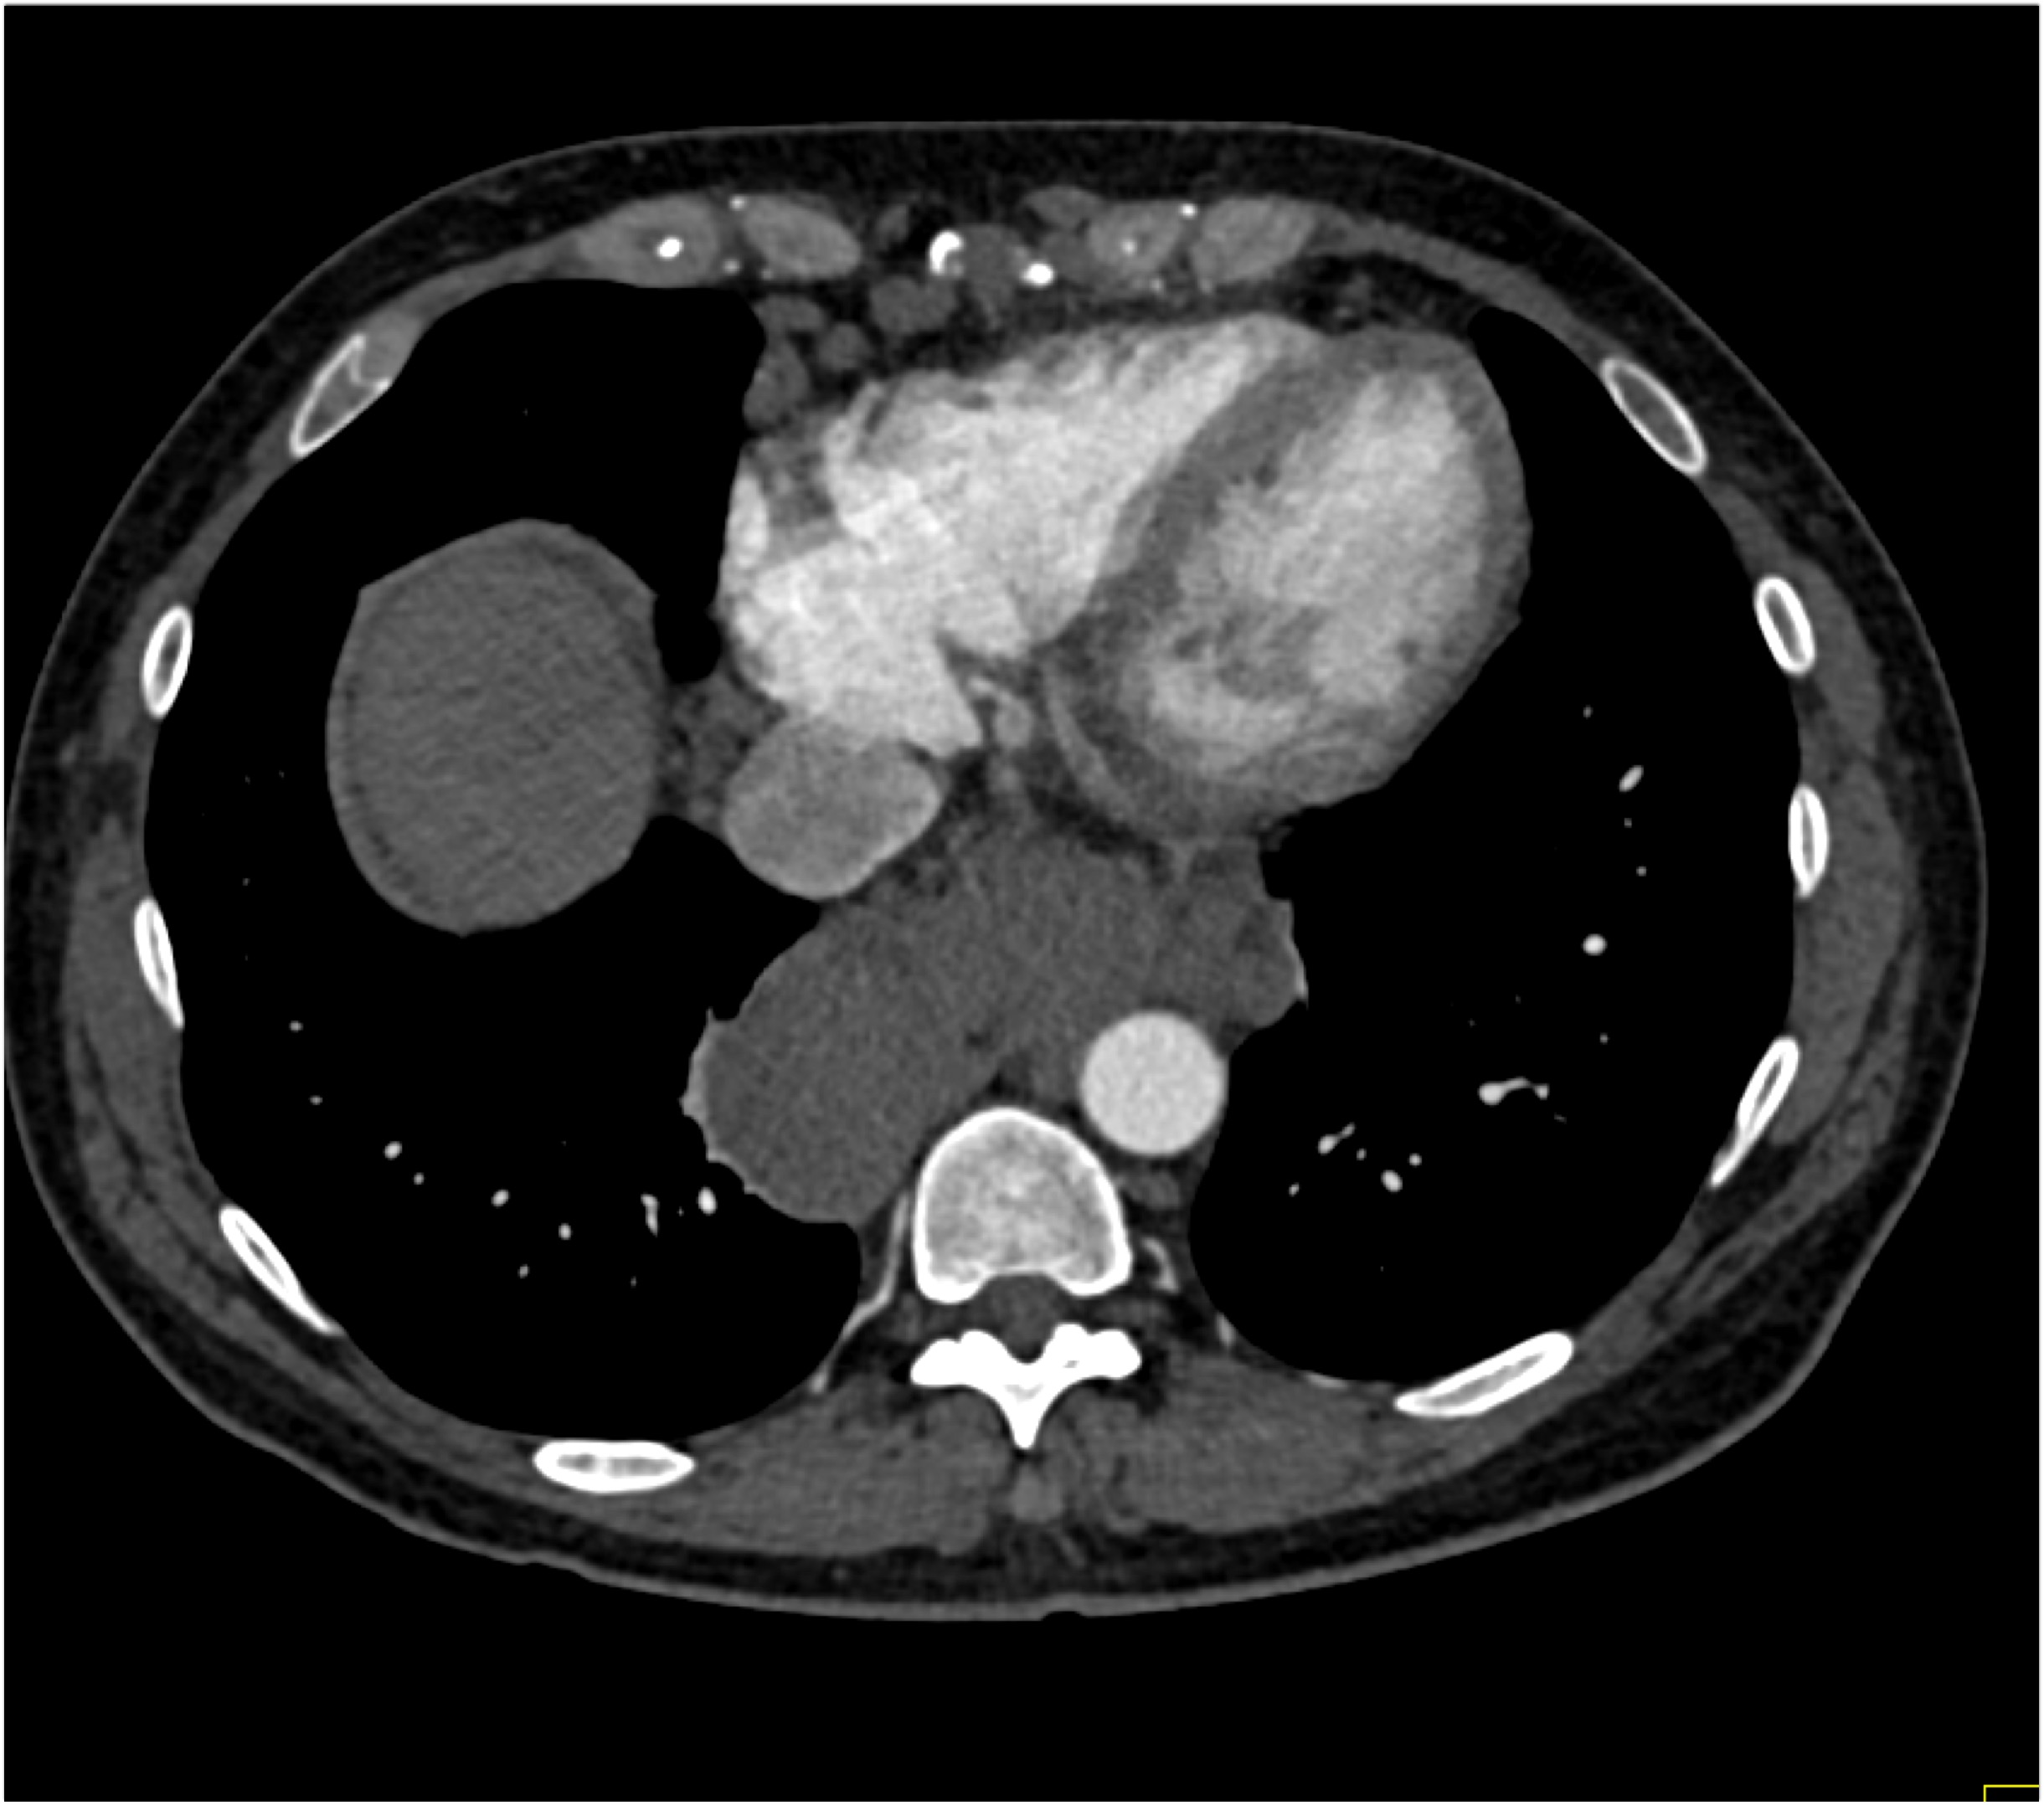

9) In this patient with chest and back pain the most likely diagnosis is?

aortic type B dissection

aortic type A dissection

intramural hematoma

giant cell vasculitis